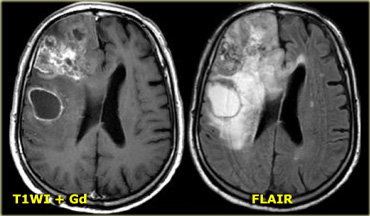

On the left is an example of a glioblastoma multiforme (GBM).

The enhancement indicates that this is a high-grade tumor, but only parts of it enhance.

Notice that there is also a cystic component with ring enhancement.

The tumor cells probably extend beyond the area of edema as seen on the FLAIR image.

This is because gliomas grow infiltratively into normal brain - initially without any MR changes.

On the left are images of a tumor located in the right hemisphere.

Although is a large tumor, the mass-effect is limited.

This indicates that there is marked infiltrative growth, a characteristic typical for gliomas.

Notice the heterogeneity on both T2WI and FLAIR.

There is patchy enhancement.

All these findings are typical for a GBM.

Virtually no other tumor behaves in this way.